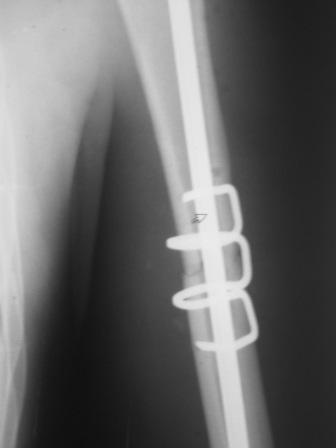

Перелом нестабильный, тактика - если позволяет сосояние больной, оперативное лечение. Как пример см. ниже, можно без скобы - стяжки с ЭПФ.

Представленный способ, функциональный, данная больная в качестве внешней иммобиллизации в течение 3-х недель полльзовалась косыночной повязкой, востановление функции плеча полное. Правда травма изолированная, но операция выполнялась через три недели после травмы, тот час после обращения ко мне - иногородняя.

У Синтеза (да и у других производителей, вероятно) есть блокируемые метадиафизарные пластины. Как раз для таких случаев. Учитывая высокую вероятность появления гетеротопических оссификатов на фоне ОЧМТ, успех во многом будет определяться стабильной фиксацией, санацией посттравматической гематомы, профилактикой послеоперационной гематомы (адекватный дренаж, эластичное бинтование), ранней разработкой движений.

Да, как раз блокированная пластина и стоит, не синтезовская метадиафизарная, Рыбинская, но на порядок дешевле, а профилактика всех осложнений - в данном конкретном случае, начало ранней на вторые сутки - после удаления дренажа разработки движений в смежных суставах. Если же идти с ревизией т.е. всё равно, открыто как вариант небольших разрезов при поперечном переломе можно и комбинированный мос (см.на вкладыше), хотя думаю для такого способа перелом всётаки низковат.

Всё правильно, просто я несколько разрозненно пытался сказать на частных примерах, то , что Вы систематизировали. Совершенно верно данный перелом можно и так и эдак, наиболее оптимально антеградное штифтование, хотя я бы предпочёл пластину LCP(просто - ну лучше у меня это получается и всё, а больному не вредит тот же функциональный способ). А низковато для неблокированного штифтования с конструкциями с термомеханической памятью, то, что представленно на втором снимке.